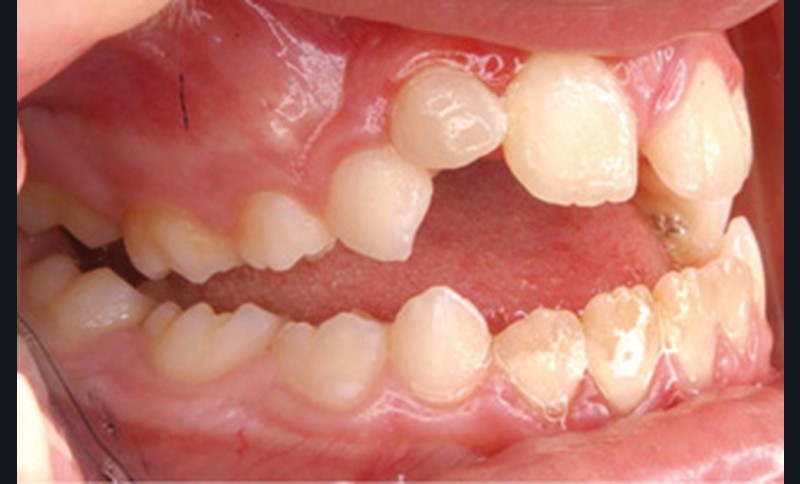

Cette patiente a été suivie dans le cadre d’un traitement interceptif alors qu’elle avait 9 ans. Elle présentait une endognathie maxillaire et une béance antérieure importante liées à des troubles fonctionnels évidents. En effet, l’examen clinique révélait une ventilation buccale exclusive, des ronflements nocturnes et une déglutition atypique. Nous avions noté à l’époque un manque de place pour l’évolution des dents définitives et un inversé d’articulé bilatéral. Les parents avaient rencontré un médecin ORL, mais avaient refusé une intervention visant à enlever les amygdales. Les deux canines maxillaires étaient incluses (fig. 1 à 6).

Quelques années plus tard, au moment de démarrer sa prise en charge orthodontique, la patiente présentait à nouveau une béance antérieure, un décalage des milieux incisifs de 2 mm et le problème transversal avait récidivé. Lors de l’examen clinique, elle présentait un inversé d’occlusion bilatéral postérieur et une ventilation buccale exclusive. À la suite du refus de réaliser l’amygdalectomie de façon précoce, elle ronflait toujours et sa déglutition ne s’était pas modifiée malgré des séances d’orthophonie (fig. 7 à 15).